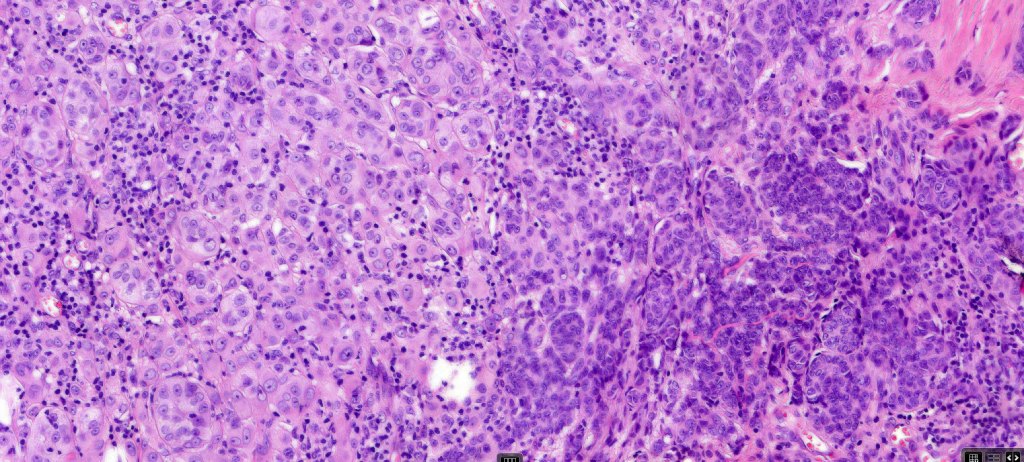

Combined Spitz & common blue nevus